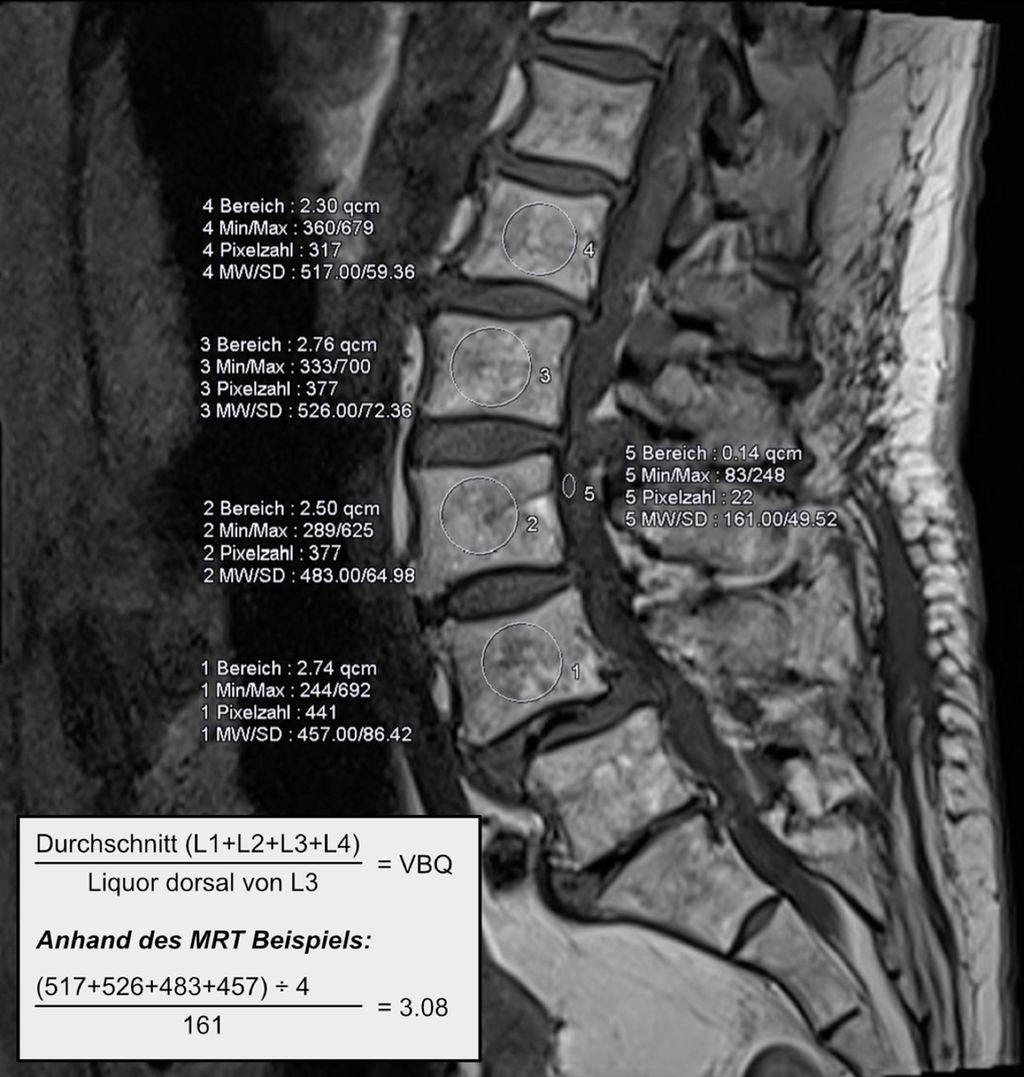

Lässt sich ein Assessment präoperativ zeit- oder strukturbedingt nicht durchführen, können jedoch bereits vorliegende bildgebende Befunde als Informationsquelle genutzt werden. Ein Beispiel ist der MRT-basierte Vertebral Bone Quality Score (VBQ), der im Jahr 2021 von Ehresman et al. beschrieben wurde.9 Die Ermittlung des Wertes wird in Abb. 1 erläutert. Ein anderes Beispiel stellt die Bestimmung der Hounsfield Units (CT-HU) aus einem CT-Scan dar. Ein eindeutiger Cut-off-Wert für den VBQ-Score liegt noch nicht vor, rezente Daten legen jedoch eine Grenze bei ca. 2,4 nahe.10Grundsätzlich besteht eine gute Inter-Rater-Variabilität und die Korrelation mit DEXA-Werten ist gegeben, jedoch kann der VBQ-Score keine DEXA-Messung ersetzen.11 Im Alltag stellt er allerdings eine einfache Möglichkeit dar, Informationen zur Knochendichte zu erlangen, wenn keine rezente DEXA-Messung vorliegt.

Abb. 1: Ermittlung des MRT-basierten Vertebral Bone Quality Score (VBQ) nach Ehresman J et al.9